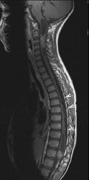

3. Other tumors: low-grade ependymomas and gliomas may affect the cervical spine and Brainstem (Fig. 7).84

Fig. 7. Neurofibromatosis type 2: Images of a 12-year-old boy with deafness and weakness in his arms and legs, whose father has bilateral deafness. Axial T2-weighted (a) and postcontrast axial (b) T2-weighted images reveal bilateral vestibular schwannomas, which are also known as acoustic neuromas (arrows). This is the classic finding of NF2. (b, c) Bilateral schwannomas are seen in Meckel's cave (arrowheads) and a (d) lower left cranial nerve schwannoma extends into the pars nervosa of the jugular foramen (arrow). (e) A part cystic and part solid enhancing ependymoma in seen within the cervical cord and medulla and within the distal cord and conus. (e, f) Thoracic schwannomas are present at numerous levels (arrowheads). Marked enhancement and thickening of the roots within the cauda equina also represent multiple schwannomas.